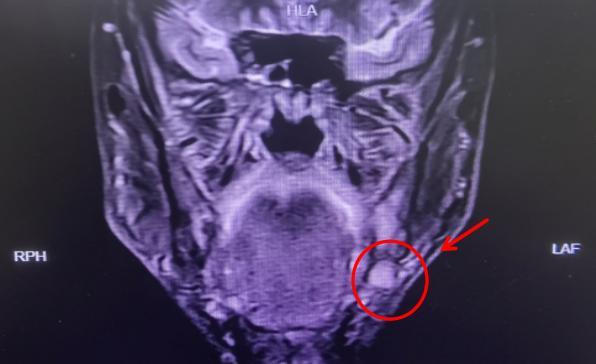

李先生因发现左侧下颌牙龈长有肿物,来到益阳市中心医院口腔科门诊就诊,切取活检样本后,病理结果显示为左侧下颌牙龈高分化鳞癌。患者随即入住口腔科病房,在完善相关检查后,发现左侧颈部淋巴结肿大,考虑淋巴结转移可能。

(▲箭头示肿瘤原发灶)

(▲箭头示颈部肿大淋巴结)